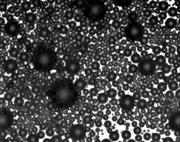

Ultrasound contrast agents, unlike agents used for other types of medical imaging, do not contain dye and ultrasound procedures do not utilize ionizing radiation. Ultrasound contrast agents are liquid suspensions of tiny microbubbles that are biocompatible and biodegradable. When they are injected into a patient's arm vein during an ultrasound exam, they pass through the circulatory system, reflecting ultrasound signals as they mimic the transit patterns of red blood cells. When an ultrasound probe is placed over a patient's heart or other organ system, the contrast agent will improve the reflectivity of the underlying region of interest. The contrast agent is essentially breathed out of the body a few minutes after it is injected.